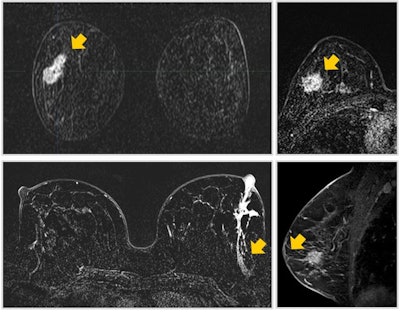

Comet sign: A lesion with enhancement characteristics that typically exhibits a "tail" that extends into the parenchyma, frequently oriented toward the nipple, resembling the tail of a comet. When a "comet tail" emerges from an enhanced lesion, it serves as a robust indicator of early ductal carcinoma in situ, particularly when it points toward the nipple or aligns with the ductal system. Less probable scenarios, which can be readily discerned from the patient's medical history, include previous biopsies or surgeries in the preceding months. All images courtesy of Dr. Karina Pesce, PhD, and presented at RSNA 2023.